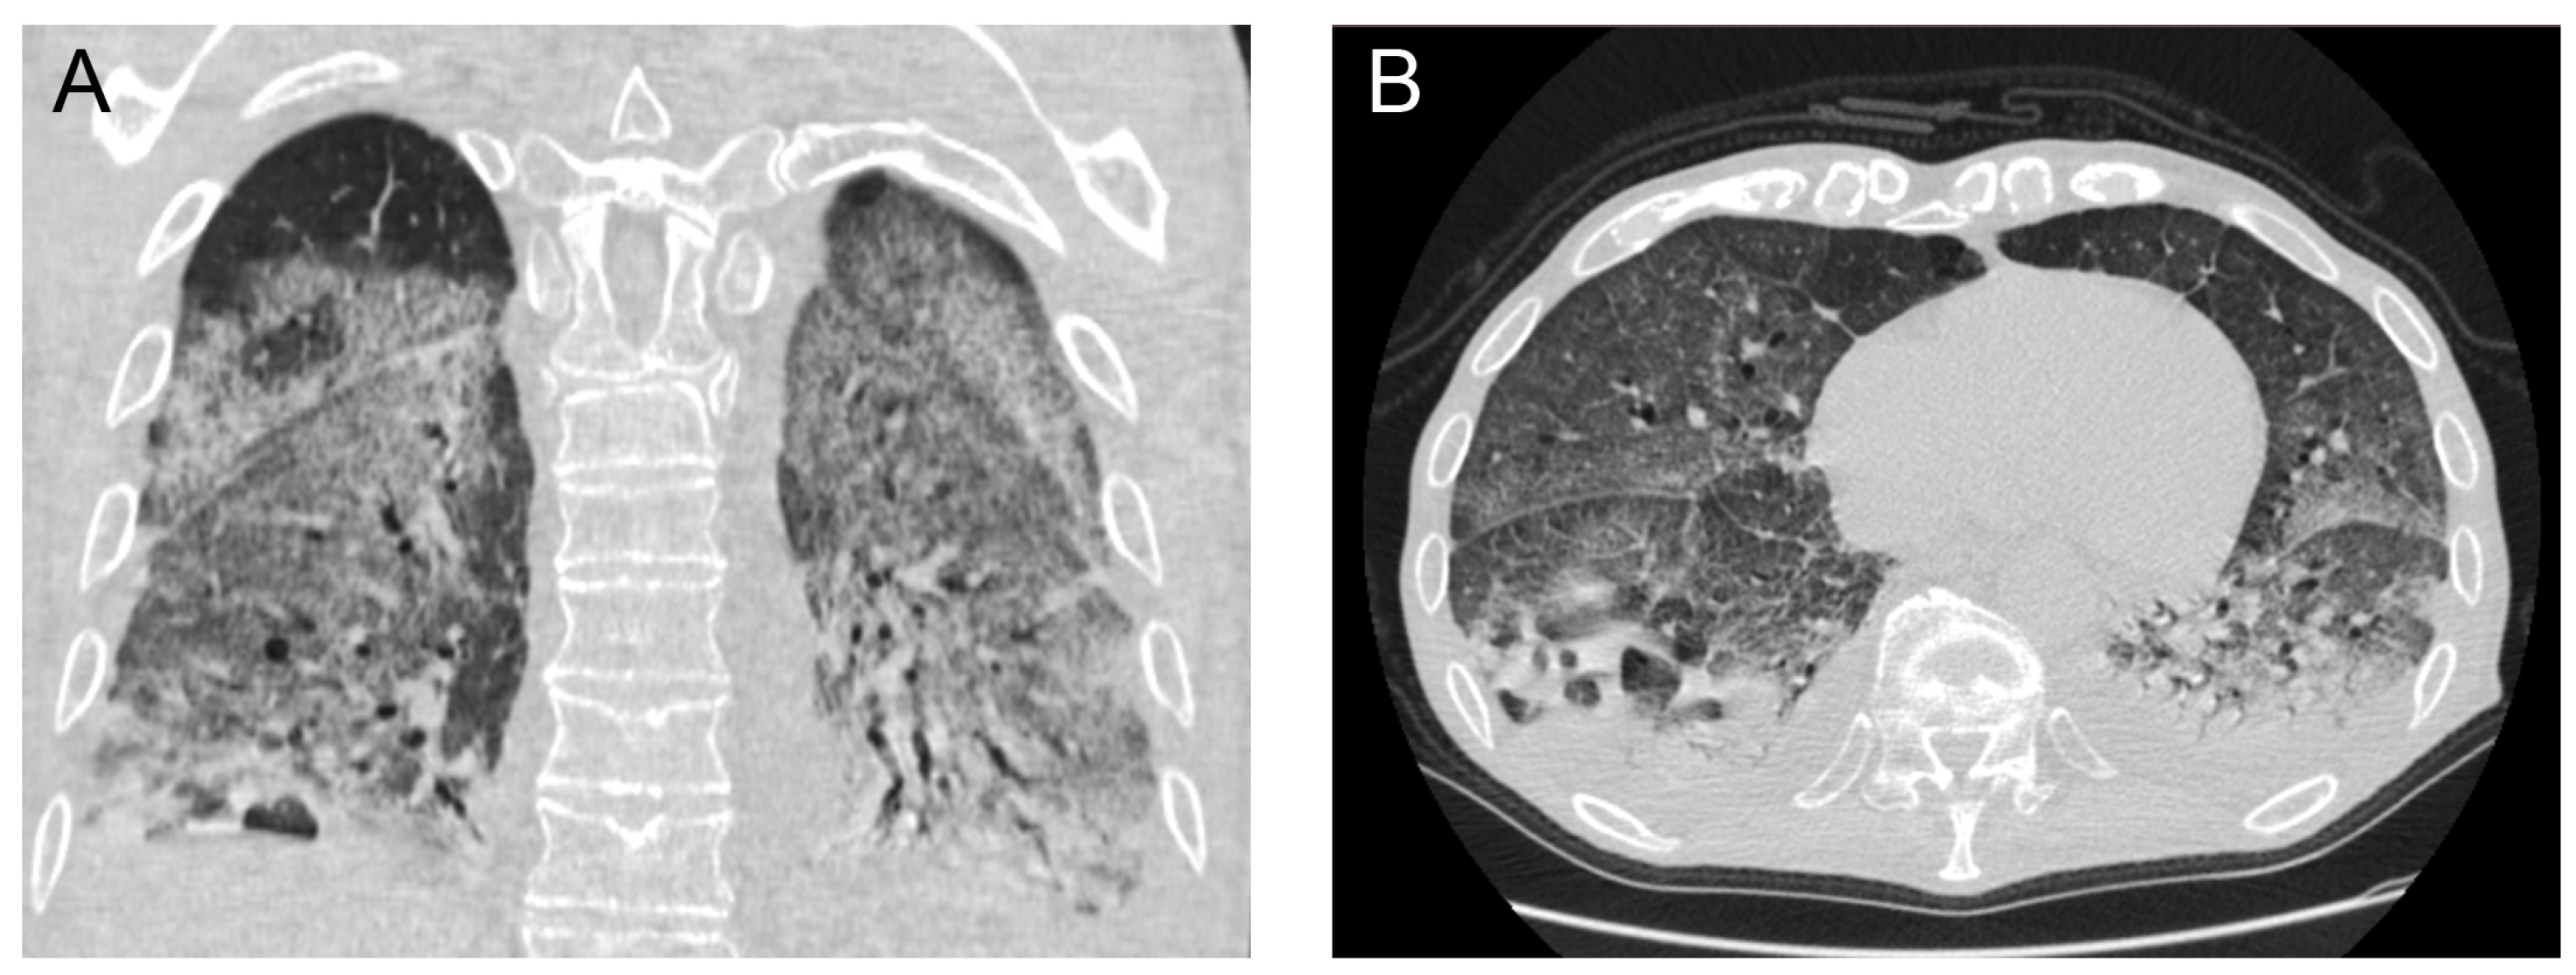

A repeat chest CT scan demonstrated multiple converging consolidated lesions in both lungs with scattered areas of ground glass. Most notably, in the posterior basal segment of his right lower lung lobe, an intraparenchymal thin-walled cavity measuring 7 × 4 cm2 in diameter was observed. The presence of an air-fluid level was indicative of a pulmonary abscess associated with the previous areas of dense consolidation (Figure 2). It was hypothesized that the pulmonary abscess was possibly associated with a bacterial superinfection caused by the COVID-19 disease. Due to unstable respiratory conditions, bronchoscopy was not performed. However, direct cultures were obtained via thoracentesis under ultrasound guidance and fluid aspiration. Both blood and aspirated fluid cultures failed to identify a causative microorganism.

Figure 2. Subsequent chest CT scan demonstrating a 7 × 4 cm2 intraparenchymal abscess (arrows) with an air-fluid level in the posterior basal segment of the right lower lung lobe (coronal (A), axial (B)).